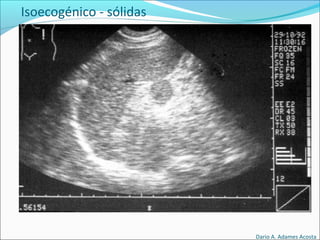

Patrones Ecográficos

Escala de grises

Depende de la densidad de los elementos y capacidad

para producir Ecos.

Isoecogénico

El elemento que nos interesa es de color similar al resto

de elementos circundantes(igual densidad).

Isoecogénicos

Isoecogénico - sólidas

• #61 Harmatomas, tumores benignos